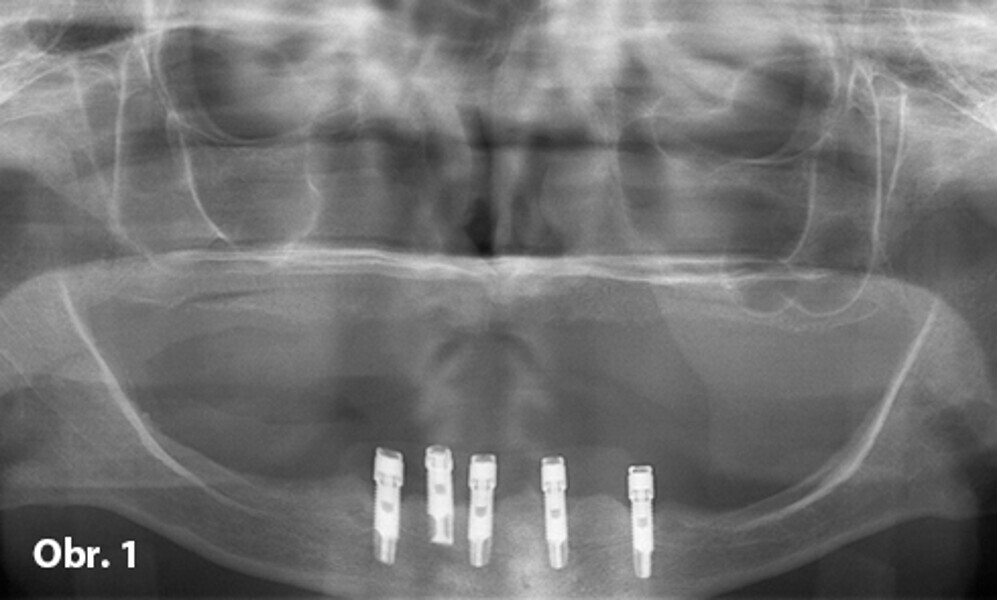

Možnosti ošetření bezzubého oblouku